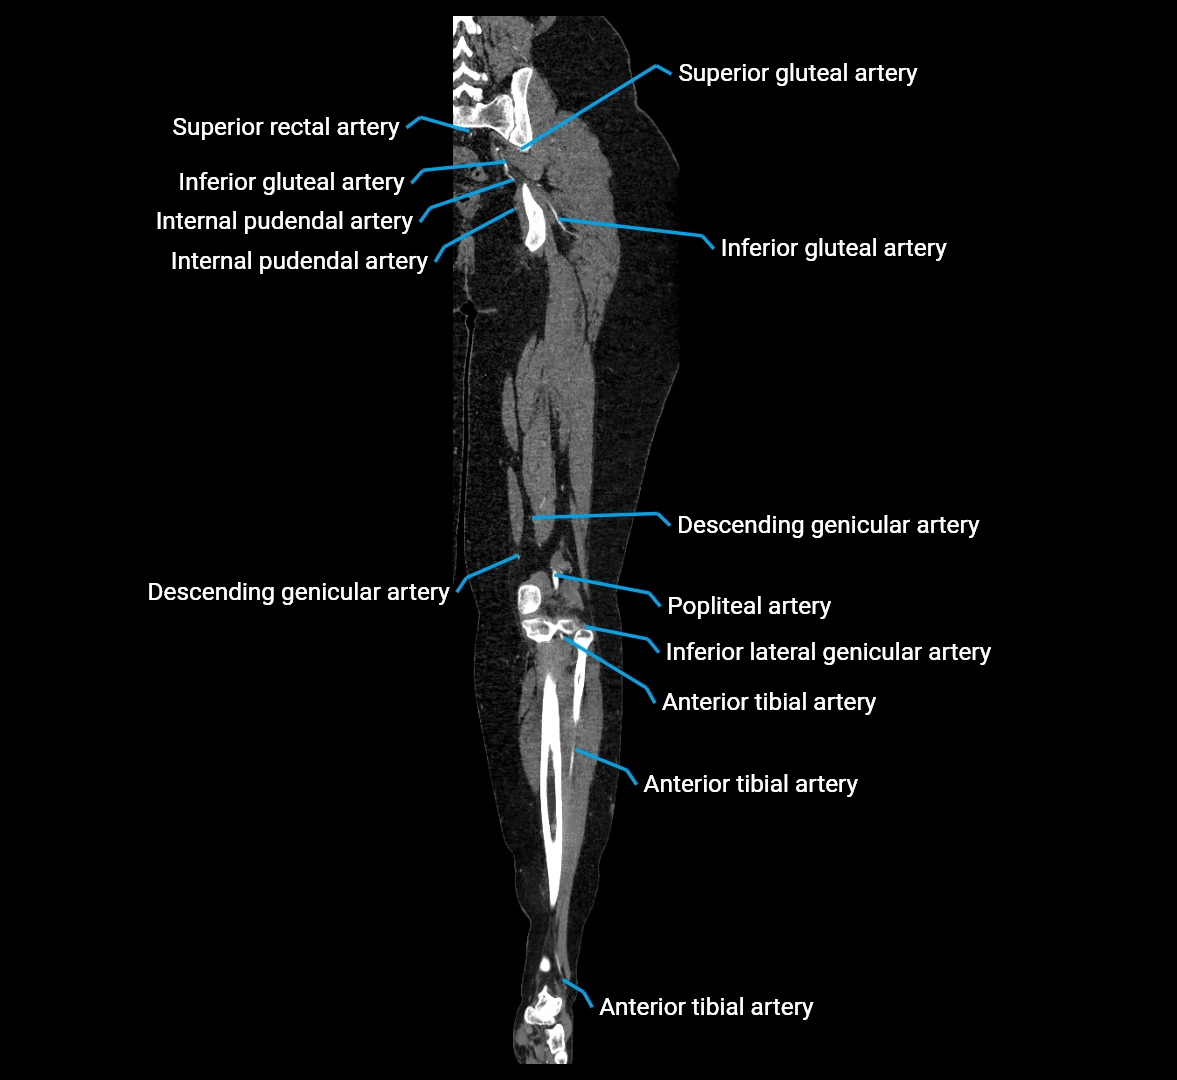

Contrast-enhanced CT (CTA):

• Gold standard for abdominal aortic imaging

• Provides excellent detail of lumen, wall, aneurysm, thrombus, and branch vessels

• Multiplanar and 3D reconstructions help in aneurysm measurement, stent graft planning, and dissection evaluation

• Detects acute rupture, traumatic injury, or occlusion with high sensitivity